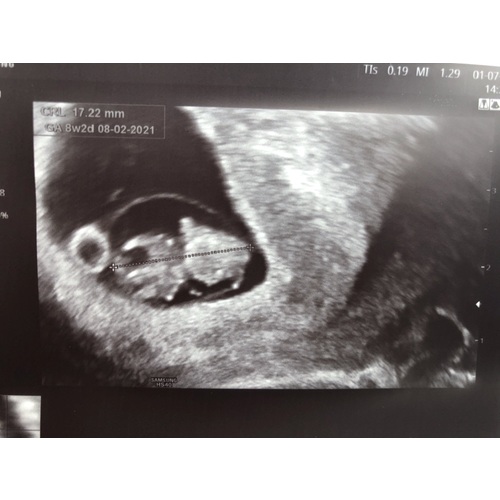

Ja! Maandag een echo (uitwendig) gehad met 8+2. Mooi hartje gezien 😊